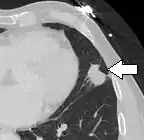

FDG-PET study of a 71-year-old woman with a solitary pulmonary nodule (thin arrow) in the left lower lobe near the heart. The scan also revealed abnormal increased activity at the gastro-esophageal junction (thick arrow). The final diagnosis was non-Hodgkin lymphoma at both sites.

If there is an intermediate risk of malignancy, further imaging with positron emission tomography (PET scan) is appropriate (if available). It can be done simultaneously as a CT scan in the form of PET-CT. Around 95% of patients with a malignant nodule will have an abnormal PET scan, while around 78% of patients with a benign nodule will look normal on PET (this is the test sensitivity and specificity).[15] Thus, an abnormal PET scan will reliably pick up cancer, but several other types of nodules (inflammatory or infectious, for example) will also show up on a PET scan. If the nodule has a diameter of less than one centimeter, PET scans are often avoided because of an increased risk of falsely normal results.[15][16][17] Cancerous lesions usually have a high metabolism on PET, as demonstrated by their high uptake of FDG (a radioactive sugar).